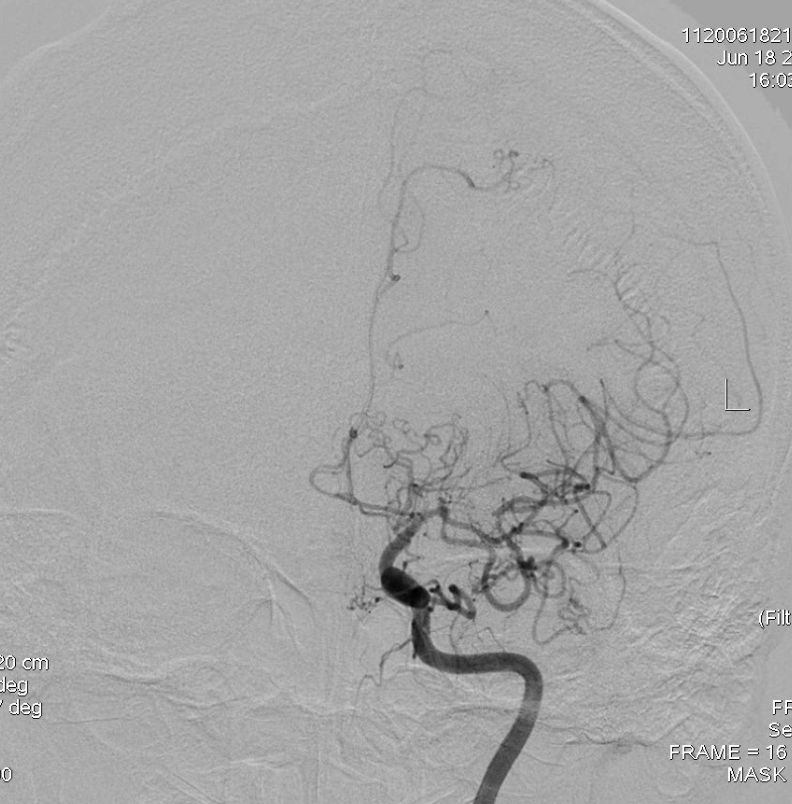

左侧大脑中动脉闭塞:

但是左侧是大脑中动脉闭塞:

造影显示右侧大脑前明显变细,大脑中只有很少的分支:

左侧大脑中分支更少,虽然正位看还有一些分支,但是侧位看,大脑半球上外侧面大面积的区域没有血液供应,尤其功能区: